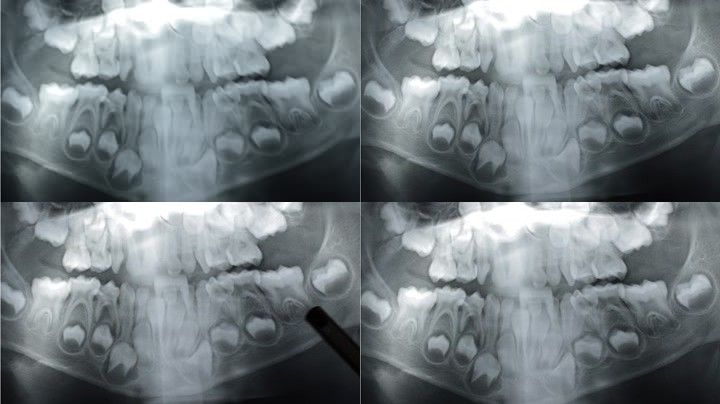

儿童面部x光 牙齿,面部x光

x线片上的一种专用x线机,能显示上腭,鼻腔,下颌骨的结构和全部牙齿

没换牙的小孩的x光图

儿童牙齿x光片

4岁儿童牙齿x光片